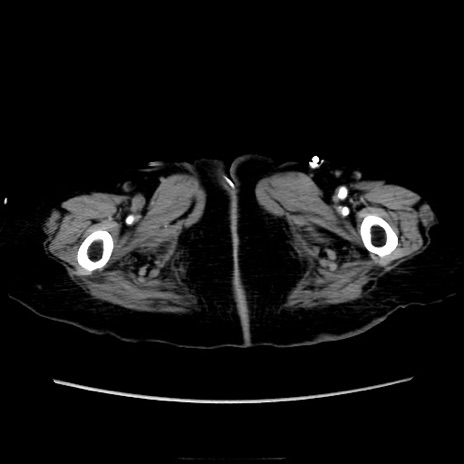

症例40(横断像)

【症例】90歳代女性

【主訴】腹痛・嘔吐

【現病歴】 食欲低下、嘔吐があり昨日他院受診。肺炎と診断され入院となる。入院後より腹部全体に圧痛あり。胃管留置され経過みていたが、症状持続するため、

当院転院となる。

【既往歴】胸椎圧迫骨折、胆石症

【身体所見】腹部:中央に激痛あり、圧痛あり、反跳痛不明

【データ】WBC 17100、CRP 18.82

横断像